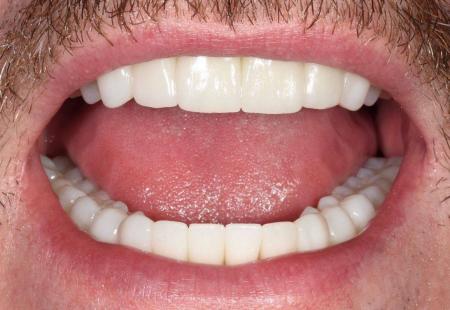

Совместные работы врача стоматолога-хирурга Семеновой Ксении Сергеевны и врача стоматолога-ортопеда Лежениной Елена Святославовна, зубной техник Дрындин Вячеслав

Реабилитация в течении одного года. Два комплекта временных коронок, дентальная имплантация на верхней челюсти по хирургическому шаблону, одномоментная нагрузка в течении 5 дней. Постоянное протезирование керамическими коронками из диоксида циркония

Протезирование керамическими коронками из диоксида циркония на имплантах

Тотальная фунцкионально-эстетическая реабилитация пациента по системе все на all-on-6

Планирование и протезирование проведено полностью в цифровом протоколе.